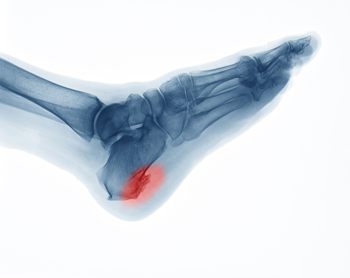

A spur is a bony growth that may develop due to repetitive irritation or stress. As its name suggests, a heel spur develops on the heel bone or calcaneus. More specifically, it typically forms in one of two places on the heel bone. An inferior calcaneal spur forms underneath the heel bone and is associated with plantar fasciitis, a common ligament injury in the foot. A posterior calcaneal spur forms on the back of the heel bone and is associated with Achilles tendonitis. Heel spurs can be asymptomatic or cause sharp pain, dull aches, stiffness, and numbness in the affected heel. Corns and calluses also often form over the affected area. If you have painful heels, please see a podiatrist for a diagnosis and treatment.

Heel spurs are formed by calcium deposits on the back of the foot where the heel is. This can also be caused by small fragments of bone breaking off one section of the foot, attaching onto the back of the foot. Heel spurs can also be bone growth on the back of the foot and may grow in the direction of the arch of the foot.